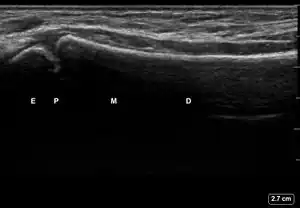

| 3 | Cortical Break Fracture | "Broken" | Break, step or gap in bone cortex which appears as a black zone in the bright, sharp white line[10][11][14][15][16] | ![]() Ultrasound dorsal view of cortical break fracture of radius (shown by arrow). E = epiphysis; P = physis; M = metaphysis; D = diaphysis. |